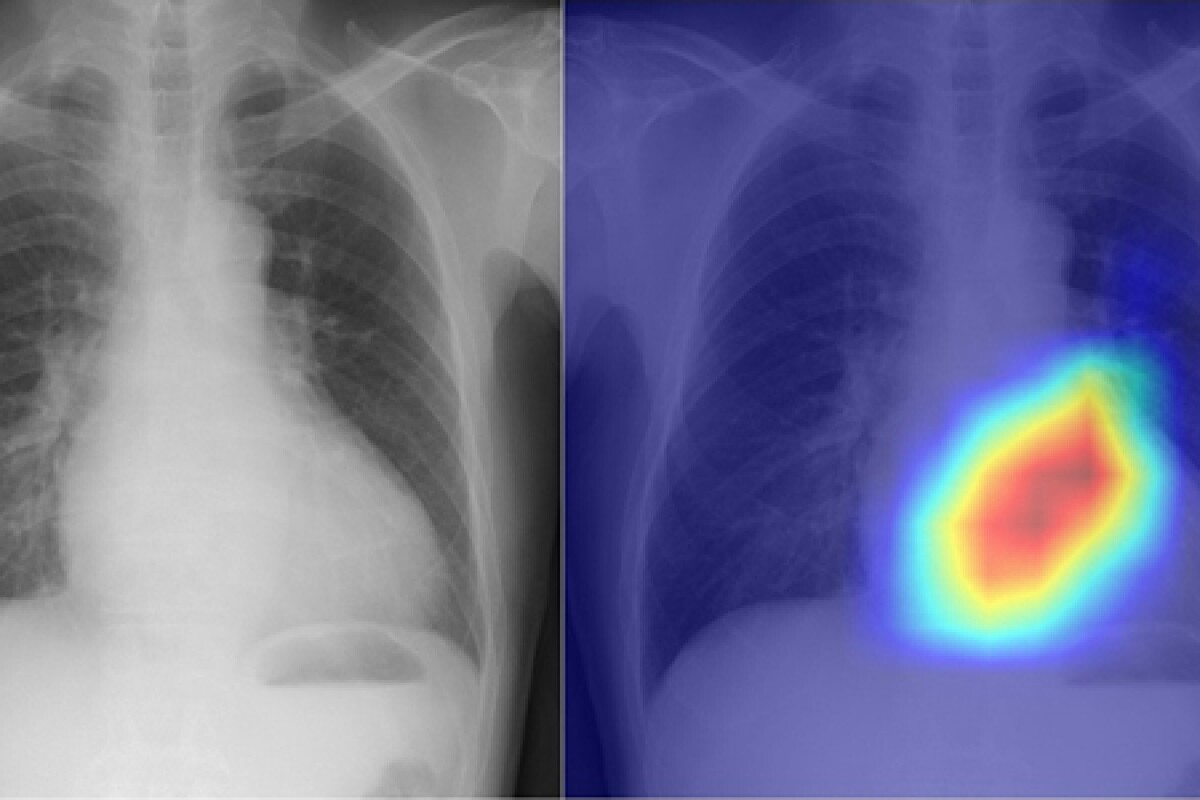

Recognizing Classic Radiographic Patterns of Pneumonia

Pneumonia shows different radiographic patterns, each with unique features. These patterns help doctors diagnose and understand pneumonia’s severity.

Lobar Consolidation: Appearance and Distribution

Lobar consolidation means one or more lung lobes are filled with fluid and cells. This is often seen in pneumococcal pneumonia. The affected area looks consolidated and white on X-rays.